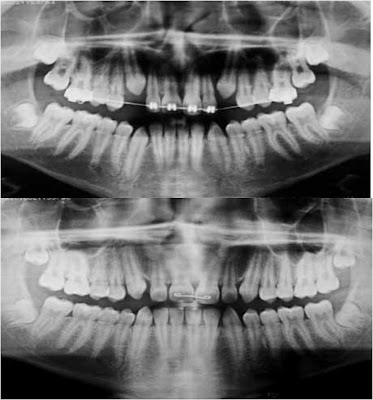

Em um artigo clássico de 1980 relacionando os fatores envolvidos com a oclusão do segmento anterior, Tuverson inferiu que a redução de esmalte de 0,3mm para os incisivos inferiores e 0,4mm para os caninos inferiores pode ser realizada sem prejudicar a vitalidade dentária. Radiograficamente, existe esmalte suficiente para permitir o desgaste dentário sem comprometimento da face proximal. Enfatizou que a opção pelo desgaste dentário seria a alternativa mais indicada para casos limítrofes de extração.

O procedimento de desgastes interproximais pode ser realizado para correção da falta de proporcionalidade dentária, ou seja, casos que apresentam discrepância de Bolton. Além disso, constitui uma alternativa para os casos com apinhamentos moderados de até 2mm para dentes anteriores e 4mm para dentes posteriores, sendo 2mm para cada hemiarco.

A saúde dentária e periodontal podem ser preservadas por meio deste procedimento, desde que os limites biológicos sejam respeitados, o que implica em não ultrapassar o limite de aproximadamente 0,25mm de desgaste em cada face de esmalte proximal dos dentes anteriores e 0,5mm para os dentes posteriores. Este procedimento mantém uma espessura de esmalte aceitável biologicamente, resguarda a proporção mínima entre coroa e raiz no sentido mesiodistal e evita alterações periodontais em virtude da proximidade radicular inadequada.